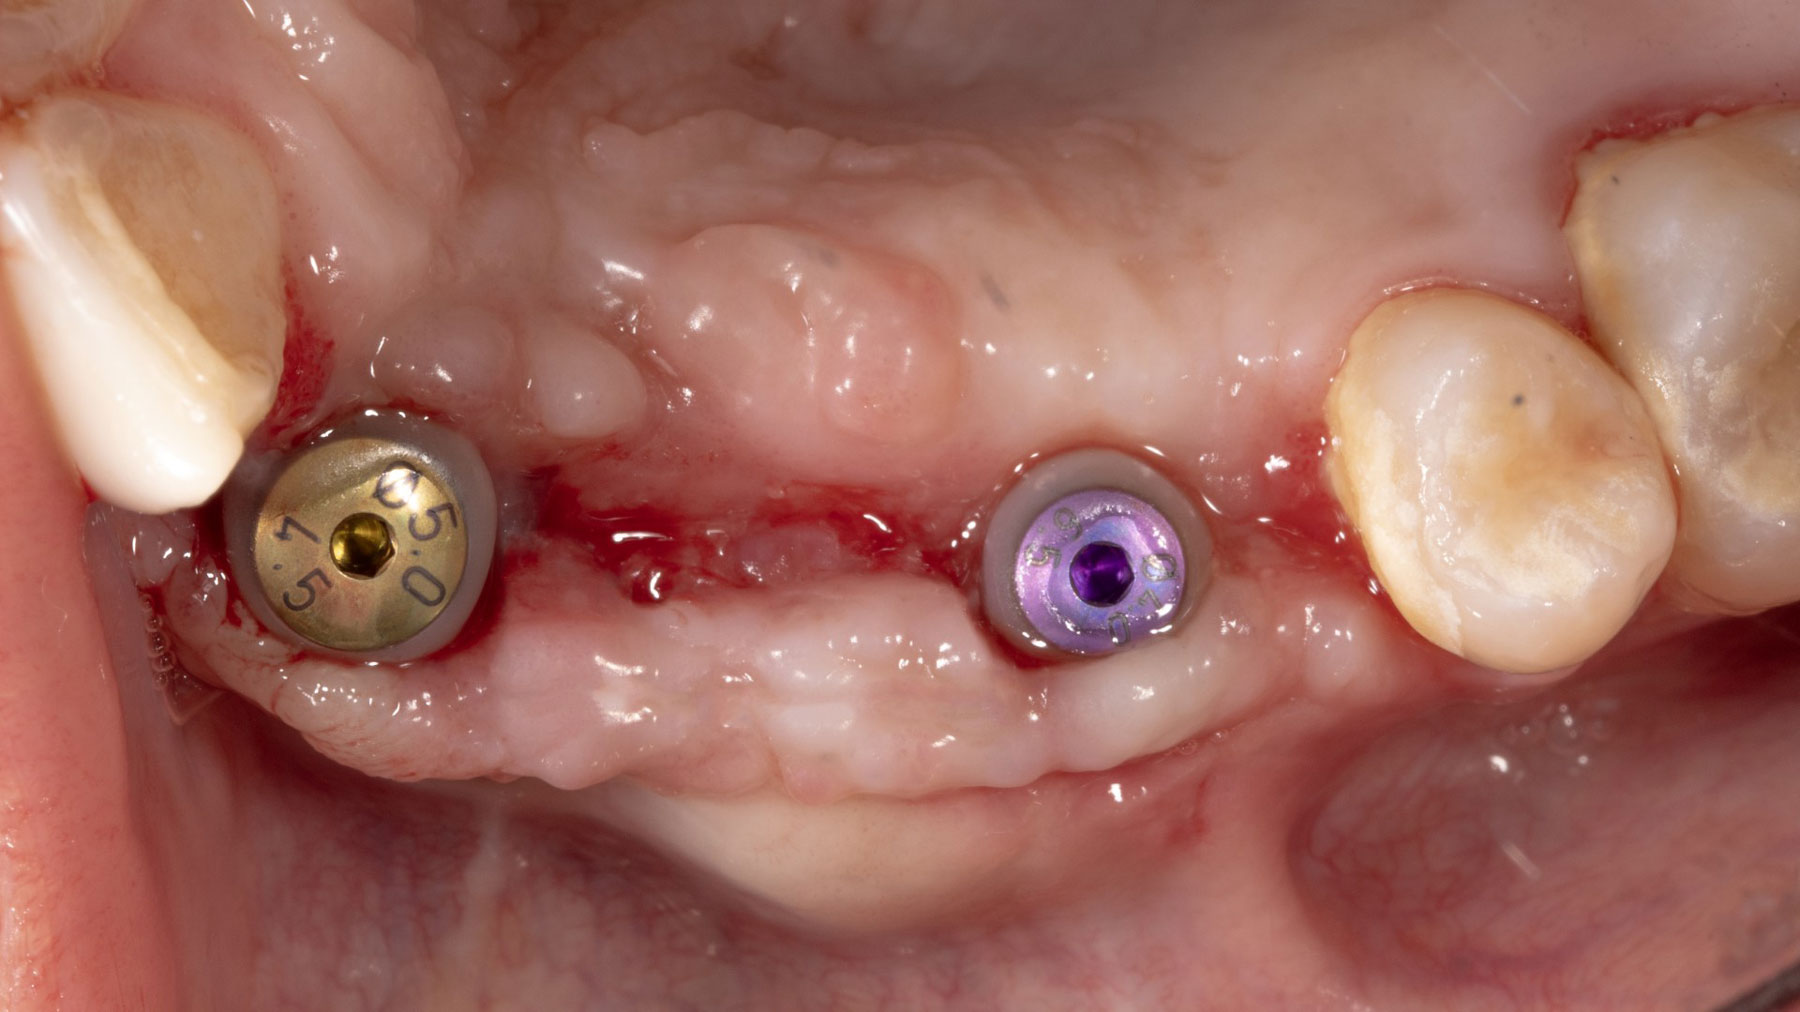

Vertical ridge augmentation was performed using allogenic cortical plates fixed with microscrews to create a stable, space-maintaining box, which was densely packed with vallos® mineralized cortico-cancellous granules hydrated with the rhPDGF-BB component of GEM 21S®. Five months later, the implants were placed, and the peri-implant soft tissue phenotype was enhanced using Geistlich Mucograft® and Geistlich Fibro-Gide® to improve soft-tissue height and thickness.

Vertical ridge augmentation of the maxillary anterior was achieved using allogenic cortical bone plates fixed with microscrews to create a box configuration, filled with vallos® mineralized cortico-cancellous granules mixed with rhPDGF-BB component of GEM21S®. At implant placement, soft tissue phenotype was enhanced using Geistlich Mucograft® and Geistlich Fibro-Gide®.